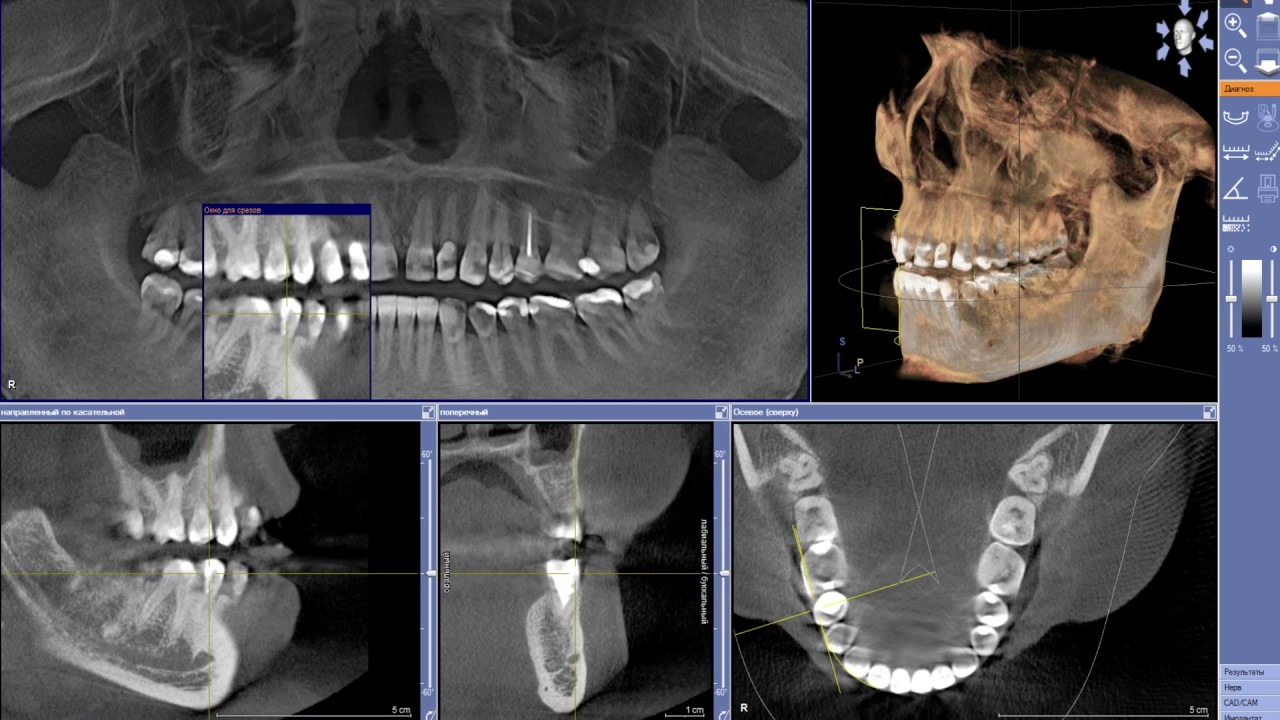

Среди прочих услуг пациентам клиники «Дока-Дент» предлагается компьютерная томография зубов (КТ), которая позволяет обследовать зубочелюстную систему в трехмерном пространстве и получить объемное 3D изображение.

Лечение любого заболевания начинается с диагностики. В стоматологической практике она чаще всего проводится с помощью рентгена (прицельных и панорамных снимков). Но рентгеновский снимок отображает объект только в одной плоскости, поэтому такой метод не всегда информативен. Дентальная компьютерная томография дает специалисту полное представление о состоянии всей челюстно-лицевой области, ведь каждый элемент зубочелюстной системы, верхнечелюстных пазух, височно-нижнечелюстных суставов может рассматриваться под разными углами, в любом измерении и при любом срезе.